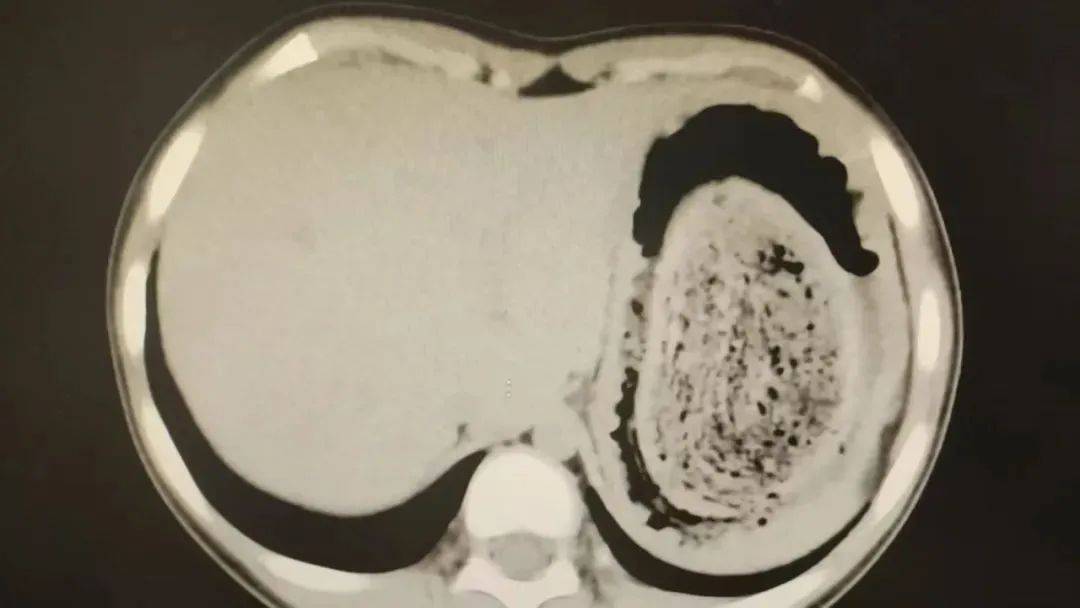

结果出来时,医生都惊呆了:小可的胃里,塞满了成团的头发,几乎占了胃容量的四分之三皇冠信用网账号申请。大量不能消化的物质,在胃酸的作用下发生变性,并与食物及其他物质结合形成团块,慢慢变成坚硬的“胃石”。

2024年10月,11岁女孩欢欢(化名)因腹痛难耐紧急送到医院,而就在两个月前,欢欢的父母发现她在拔自己的头发,偷偷吃掉皇冠信用网账号申请。经检查,医生发现她胃腔和肠管里有大块的毛絮状结石,几乎占据整个胃部。最终,一块长38厘米、宽15厘米、厚10厘米的毛发结石被取出。